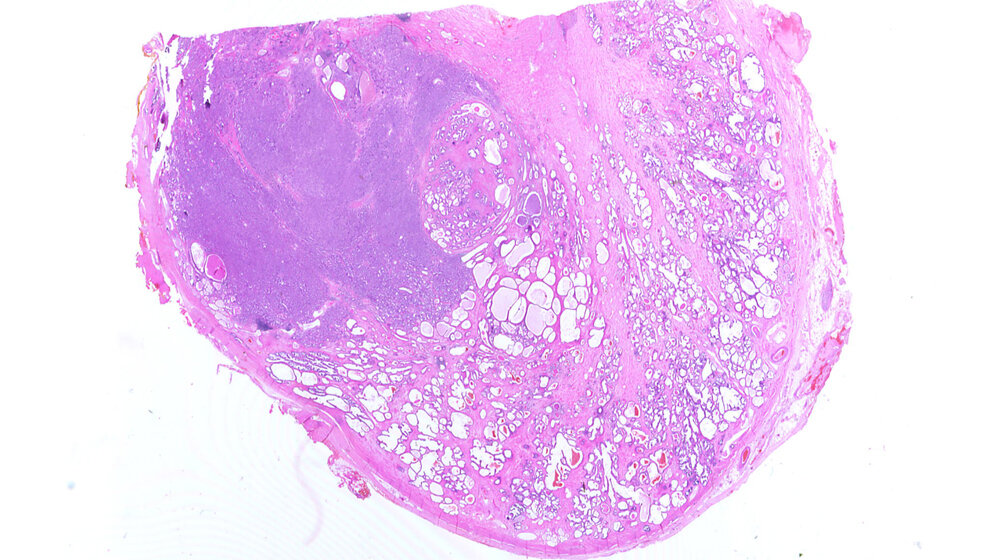

Prostata mit Adenokarzinom

Schnitt durch eine Prostata mit Adenokarzinom (links) HE-Färbung Alex_brollo, Slide files from Hospital of Monfalcone (Italy), CC BY-SA 3.0, wikimedia